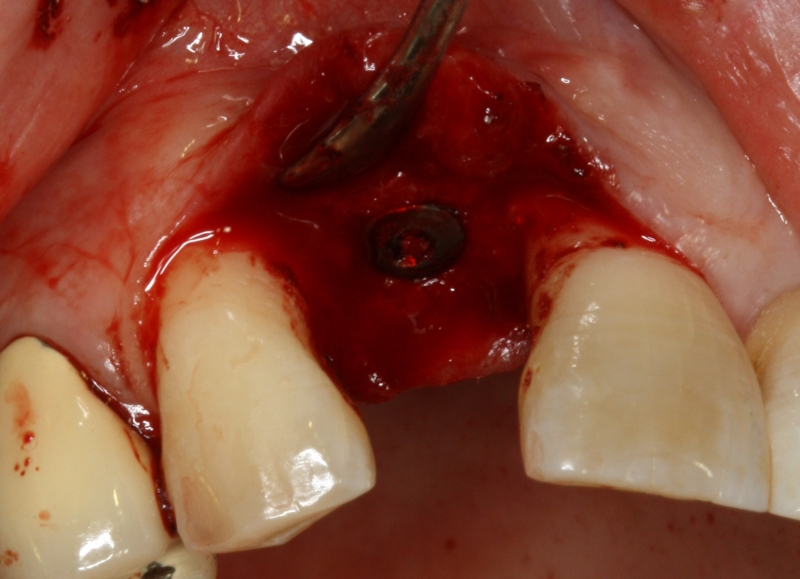

13/20 - Implant placementGBR with maxresorb® & Jason® membrane - Prof. Dr. Dr. D. Rothamel